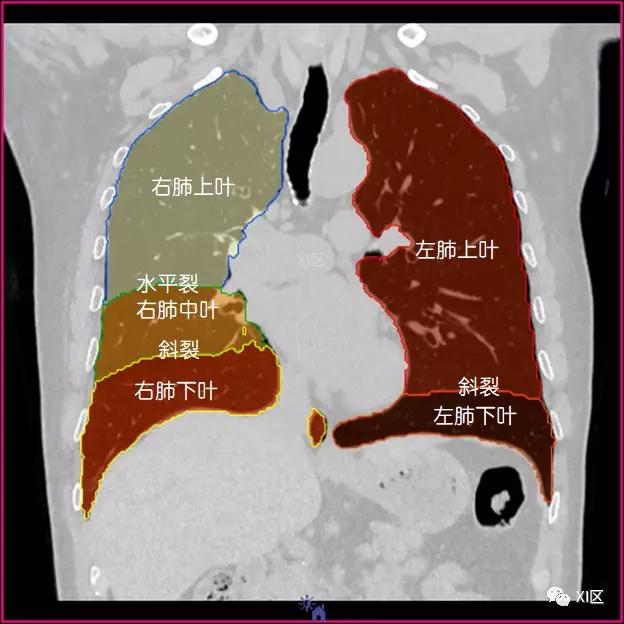

肺的分叶

左肺借斜裂成上、下两叶;右肺借斜裂和水平裂成上、中和下叶三叶。

矢状位